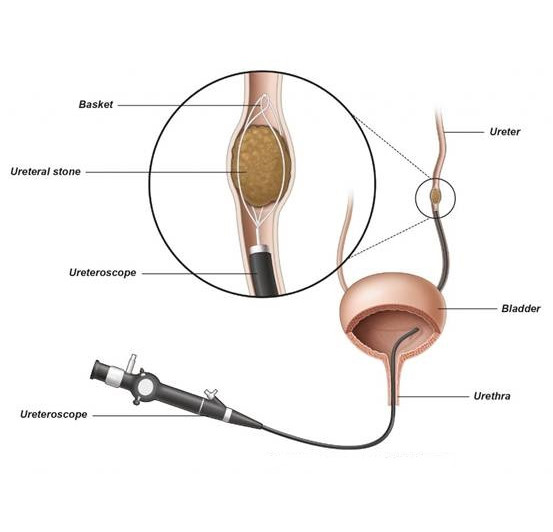

Ο ουρολόγος χρησιμοποιεί ένα λεπτό, εύκαμπτο σωλήνα που ονομάζεται ουρητηροσκόπιο και εισάγεται μέσω της ουρήθρας στην ουροδόχο κύστη, στην συνέχεια στον ουρητήρα και τελικά στο νεφρό. Ο λεπτός αυτός σωλήνας έχει μια μικροσκοπική κάμερα στο άκρο του που χρησιμοποιείται για τον εντοπισμό των λίθων. Τα χειρουργικά εργαλεία (Εικ. 3) όπως η λαβίδα σύλληψης και το basket, περνούν μέσα από ένα ειδικό κανάλι εργασίας του ουρητηροσκοπίου, έτσι ώστε ο γιατρός να μπορεί να αφαιρέσει τυχόν μικρές πέτρες.

Εικ. 3: Αφαίρεση λίθου με την χρήση ενός basket